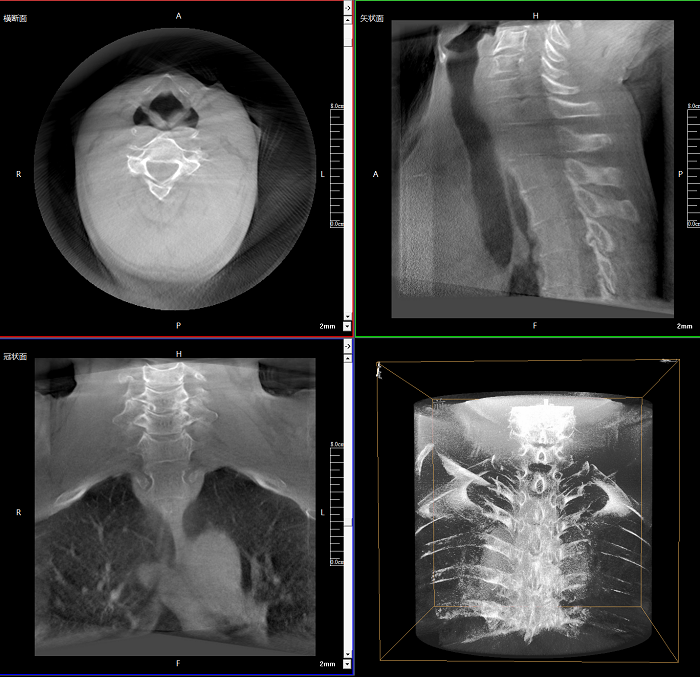

三維成像 全面觀察

任意視角、任意切面觀察

術中實時生成橫斷面、矢狀面、冠狀面及三維影像,可在任意切面、任意角度評估植入物和解剖結構的相對位置。

100%視野范圍提升

較9英寸常規(guī)平板視野提升100%,幫助醫(yī)生迅速判斷椎體節(jié)段,定位手術部位。

Clinical picture

臨床圖片